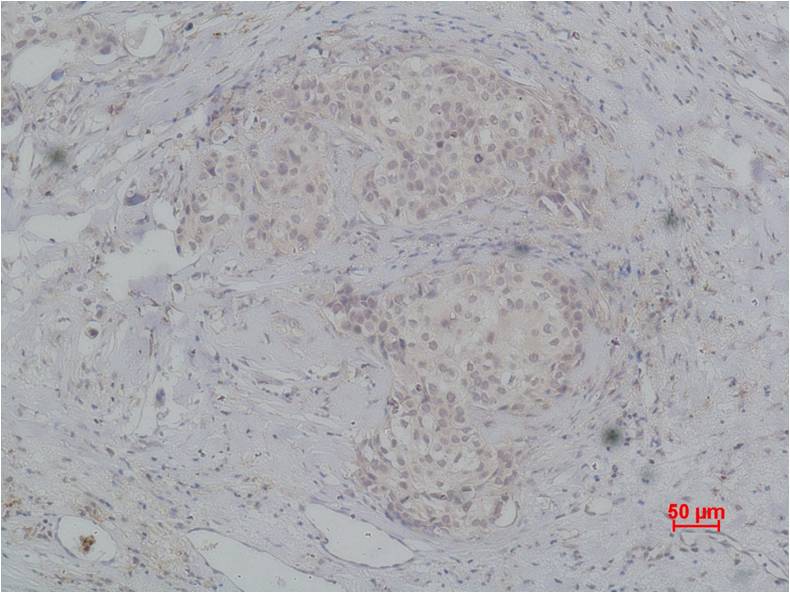

Immunohistochemical analysis of paraffin-embedded human breast caricnoma using PI3 Kinase P85β (EA210)Rabbit pAb diluted at 1:200.